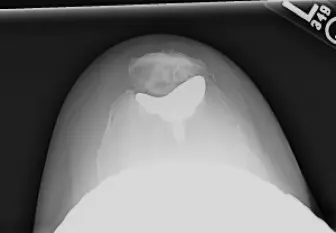

- مفصل الرضفة والفخذ: يُعد التتبع الصحيح للرضفة ضروريًا لمنع آلام الركبة الأمامية والكسر حول الطرف الصناعي. يؤثر تصميم مكون الرضفة والمحاذاة الدورانية للمكونات الفخذية والظنبوبية على ذلك.

- الأشعة السينية (X-rays): هي الفحص الأساسي لتشخيص التهاب المفاصل وتقييم مدى تلف المفصل. تظهر الأشعة السينية تضييق المسافة المفصلية، وتكون النتوءات العظمية (Osteophytes)، وتصلب العظم تحت الغضروف، وتكيسات العظم.

- الأشعة السينية الواقفة ذات الطول الكامل (Full-length Standing AP Mechanical Axis View): ضرورية بشكل خاص لتخطيط جراحة استبدال مفصل الركبة، حيث تساعد في تقييم المحاذاة الميكانيكية للطرف بأكمله.

- التصوير بالرنين المغناطيسي (MRI) أو الأشعة المقطعية (CT Scan): قد تُطلب في حالات معينة لتقييم تفصيلي للأنسجة الرخوة، أو لتحديد مدى تلف العظم، أو للتخطيط الجراحي المعقد، خاصة في حالات التشوهات الشديدة أو المراجعة.